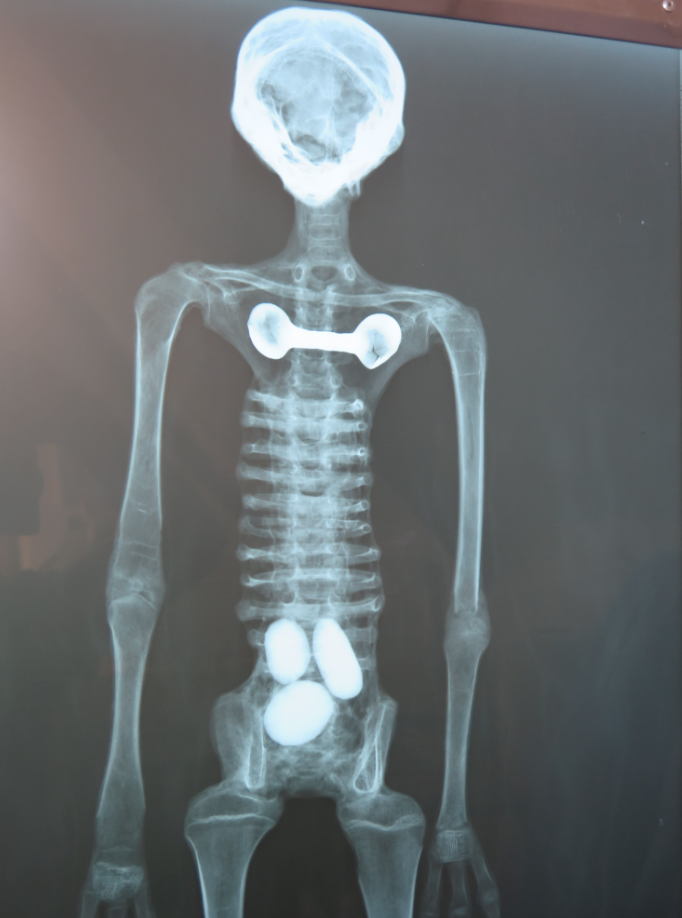

按照莫桑的説法,這些“外星人木乃伊”存在完整的內部構造,但經過X光照射分析,這些所謂的外星人全都是粗製濫造的假貨。事實上,所謂的木乃伊確實存在“骨骼結構”,但明顯不是自然生長的,而是用人和動物的骨骼拼裝而成的。脊柱、肋骨和肢體全部都是用折斷的鳥類骨骼拼在一起的,而且沒有任何關節相互連接。其中一個代號“E.V.”的木乃伊頭骨取自某種小型動物,另一些外星人的頭骨則取自猴子和美洲駝。

對這些外星人手腕的掃描後,結果就更離譜了。這些外星人的手部完全是用人類和動物骨骼胡亂拼接的,裏面甚至混雜了大量無意義的碎骨,有些指骨甚至是完全顛倒的。顯然,通過對人類和動物骨骼的打磨和重新拼接,有人制造了這些完全虛假的“外星人木乃伊”。

▲完全沒有任何章法的拼接手掌

而且,這些所謂外星人的體內沒有發現任何的內臟痕跡,外星人似乎既不會吃東西,也不會排泄,但在其中一個樣本體內居然有三顆蛋!而且,所有的外星人木乃伊都有和人類高度相似的身體構造,基本就是科幻電影裏“E.T.”的翻版。在軍武菌看來,這種造假方式實在是太缺乏想象力了。